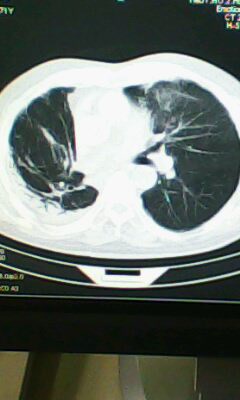

标题: CT25675:男 71 肺癌部分切除术后 3年 [打印本页]

标题: CT25675:男 71 肺癌部分切除术后 3年

两肺感染性病变,右侧肺膨胀不全,左侧上叶结节影及左侧颈部淋巴结肿大建议复查。

1)两肺感染性病变。2)右侧胸膜增厚。3)冠状动脉及主动脉钙化。

右肺癌切除术后。

右肺炎症,左肺炎症。

右侧胸膜肥厚。

两肺感染性病变\\右侧胸膜增厚

1.右肺符合肿瘤切除术后ct表现。

2.左肺炎症。

术后改变,双肺内纤维索条影考虑与放疗有关。